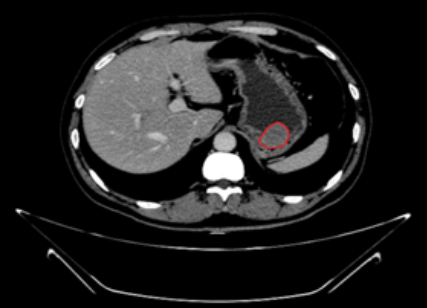

患者入住消化内科后,余细球主任建议完善胸腹部增强 CT 及超声内镜检查。通过 CT 检查也看到胃底一直径约 4.5 cm 软组织,高度怀疑肿瘤,万幸的是,周围淋巴结及邻近器官未见转移灶(图 2)。